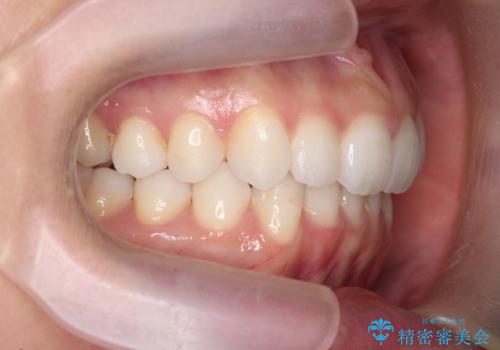

- 前歯が出っ歯のように見えることの改善を求めて来院されました。

当初、セラミックによる治療をご希望されていましたが、相談の結果矯正治療を選択されることとなりました。

通常口元の突出感の改善を行うには小臼歯の4本抜歯が検討されますが、歯のガタ付きが下顎前歯に限定していることから

下顎前歯を1本だけ抜去を行い、上顎の歯は可及的にマイクロインプラントを用いた後方移動を行い口元の印象の改善を計画することとなりました。

マイクロインプラントを用いてしっかりと後方移動を行ったことで前歯の角度は改善され、口元もすっきりと仕上げることができました。